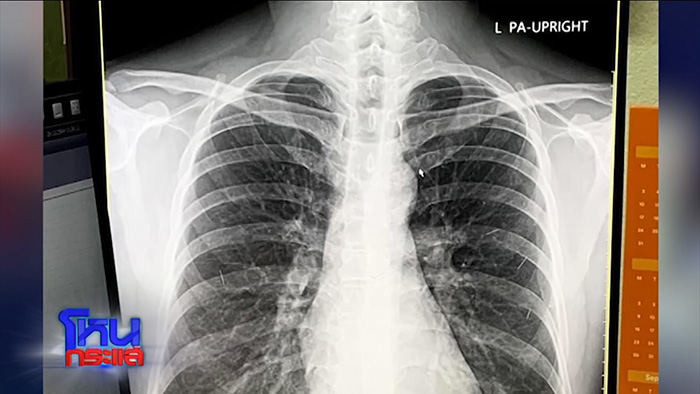

- ภาพมีเยอะมาก เห็นแล้วคุณพระช่วย มีเรื่องฟิล์มเอกซเรย์ ?

เอ : เป็นการยืนยัน การไปตรวจร่างกายเป็นช่วงปลายปี 64 หลังเกิดเหตุมาเดือนสองเดือนแล้ว เขาเอาฟิล์มเอกซเรย์มายืนยันกับเราว่าร่างกายเขาแข็งแรงแล้ว เขาดีมากนะ ขอบคุณทุกคนมากที่เสียสละ

บี : ตอนที่เขาไปตรวจสุขภาพ เขาถ่ายฟิล์มเอกซเรย์มาให้ดูว่าเขาดีขึ้นแล้ว แต่หลังจากนั้นเขายังมีความต้องการอยู่ ต้องการทำพิธีแบบเดิม ๆ อยู่เรื่อย ๆ จนเราสองคนคิดว่าน่าจะไม่ไหวแล้ว บอกตรง ๆ ผมรู้ว่าคุณเอเชื่อมั่นศรัทธารักและเคารพจริง ๆ ตอนแรกผมไม่กล้าเตือนเขา ถ้าเขาไปถามคนนั้น ถ้าคนนั้นสงสัย ผมไม่รู้ว่าคุณเอจะโดนคนนั้นหลอกอะไรอีก จนผมอาจไม่มีโอกาสได้พาเขาออกมาจากวงจรนั้นก็ได้ ผมก็เลยตัดสินใจ จนเขาบอกเองเลยว่าพอแล้วนะ ผมก็มั่นใจว่าเขาคงไม่เชื่อคนนั้นอีกแล้ว